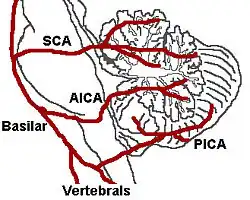

Das Wallenberg-Syndrom (synonym: Viesseaux-Wallenberg- und Wallenberg-Foix Syndrom oder auch Dorsolaterales Medulla-oblongata- oder Arteria-cerebellaris-inferior-posterior-Syndrom) entsteht durch einen Verschluss der Arteria cerebelli inferior posterior (PICA) oder der Arteria vertebralis. Als Folge davon kommt es zu einem Infarkt der dorsolateralen Medulla oblongata, die Teil des Hirnstamms ist.[1] Es ist eine seltene Form des Schlaganfalls. Die Symptome sind vielgestaltig entsprechend den jeweils betroffenen neurologischen Strukturen.

Es liegt ein Verschluss oder eine hochgradige Enge im Bereich der hinteren unteren Kleinhirnarterie (Arteria cerebelli inferior posterior) oder der Arteria vertebralis und ihrer Äste vor, die Teile des verlängerten Marks (Medulla oblongata) versorgen. Auslösend kann ebenfalls eine Hirnblutung in dieser Region sein. Es führt zu einem Infarkt am seitlichen Teil der Medulla oblongata, mit den dafür typischen Ausfallmustern. Häufigste betroffene Arterie ist die A. vertebralis.